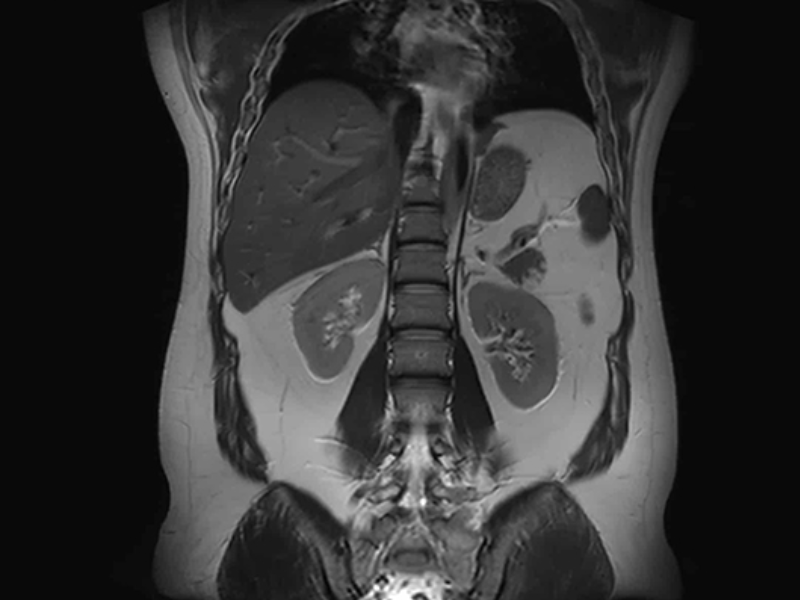

60 cm FOV T2W FSE Abdomen